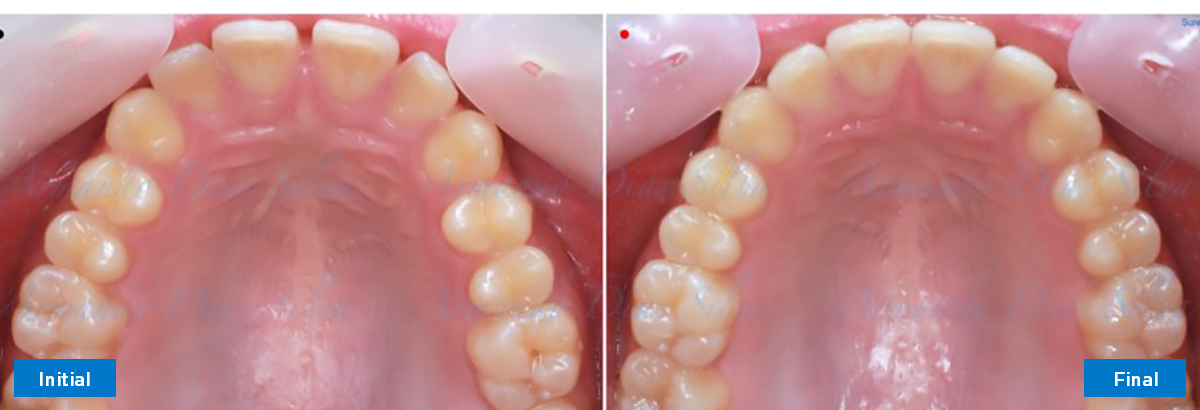

• Espaciamiento leve de las arcadas superior e inferior (deficiencia transversal de 3,45 mm)

• El primer molar superior derecho está en una posición más mesial que el primer molar superior izquierdo

• Deficiencia transversal maxilar leve (3,45 mm)

• Desrotar y distalizar los molares superiores

• Retruir los incisivos superiores

• Molares de clase I logrados con distalización y sin elásticos

• Sin expansión maxilar, respetando la envoltura periodontal